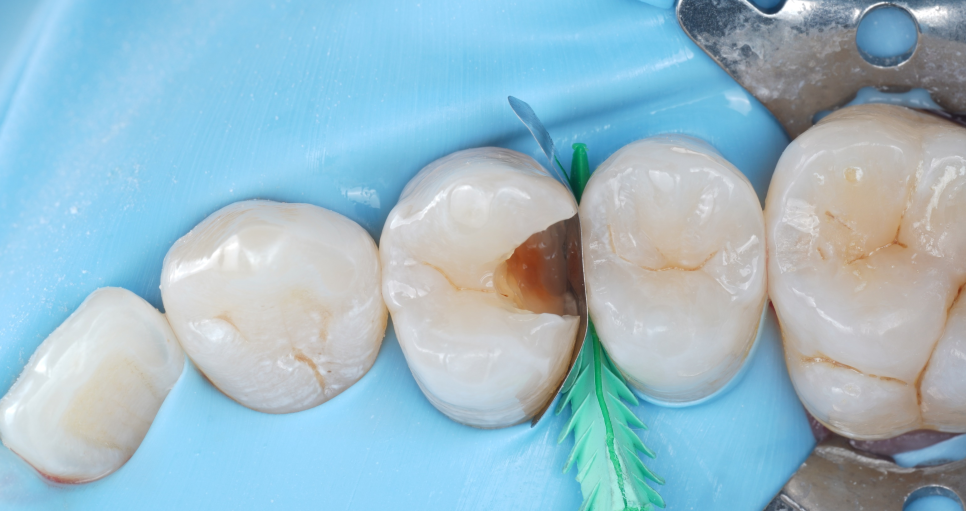

레진은 수분에 약한 재료예요.

침이 조금이라도 닿으면 접착이 약해지는데요. 치아를 보존할 수 있는 좋은 재료지만 아주 예민(?)해서 잘 다루지 못하면 금방 떨어져 버리죠.

그래서 러버댐으로

완전 방습을 시행했어요.

강남역치과

번거롭기도 하고 진료 시간도 길어져서 번거롭게 생각하시는 분들도 있지만 저는 레진 수복에 있어 제일 중요한 원칙으로 생각하고 있어요.

촬영일 : 251020

충치 부위를 깨끗하게 제거한 뒤 Se-bond를 사용해 접착층을 형성하고 여러 층으로 쌓아 올렸어요.

각 층마다 빛을 이용해 단단하게 굳힌 뒤 자연치와 같은 질감과 색을 만들어냈죠^^